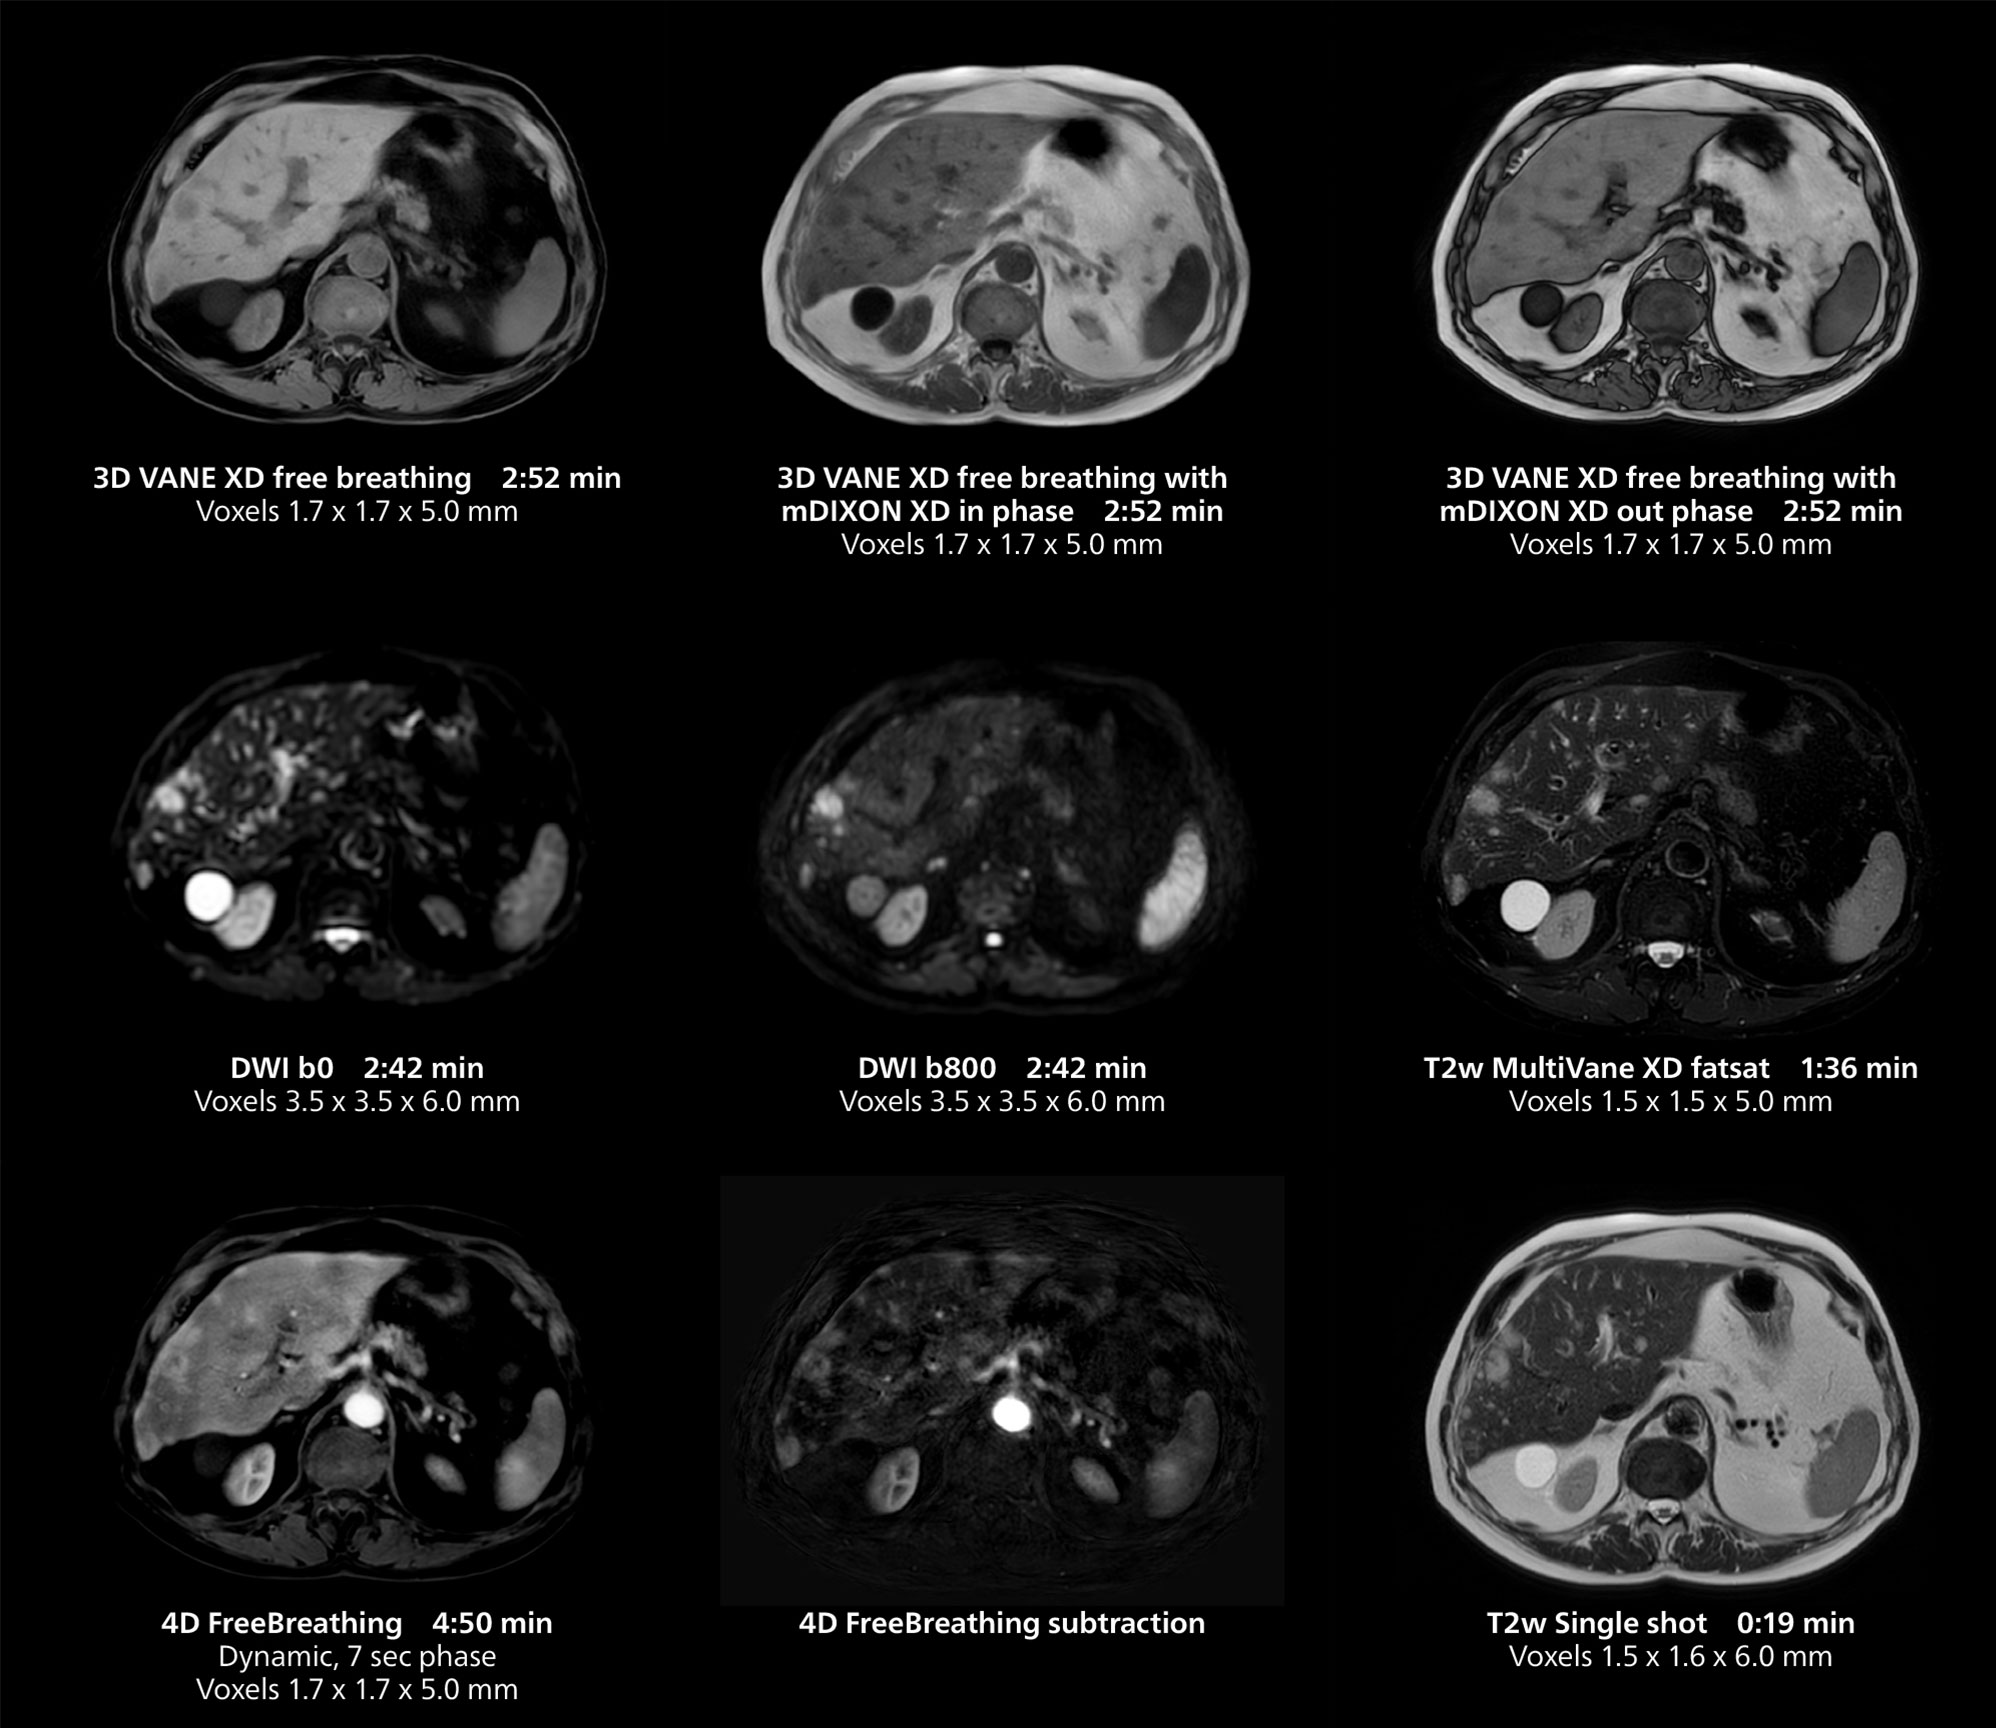

This case includes 3D free breathing and 4D dynamic free breathing MRI of a metastasized liver. A high quality fatsat sequence with good resolution is obtained in 1:36 minutes with T2-weighted MultiVane XD.

Dr. Gellée highlights the robust free-breathing scans as “the feature that makes the biggest difference in my daily work. The 3D free breathing sequences are very reproducible, and the axial acquisition is very good. For example, in endometriosis, which is one of my focus areas, it provides high contrast and good resolution so that I can see small details. We also use free breathing for liver and pancreas imaging. In multi-phase liver studies, 4D Free Breathing delivers 3-second temporal resolution, making a dynamic scan with more than one arterial phase possible.”

She also uses free breathing with 3D mDIXON to obtain in-phase, water and fat images in a single scan. “It is very reproducible before and after gadolinium, which makes it useful for liver imaging,” she adds.